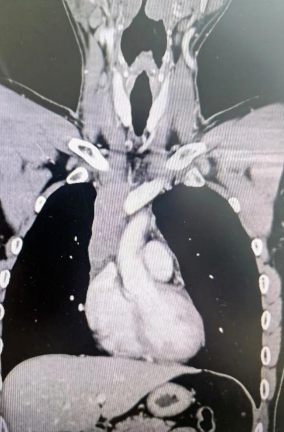

經(jīng)檢查發(fā)現(xiàn)患者前上縱隔腫瘤已經(jīng)完全侵犯了我們?nèi)梭w最主要的大靜脈之一——上腔靜脈,導(dǎo)致上腔靜脈回流嚴重受阻并導(dǎo)致由上腔靜脈起至左側(cè)無名靜脈、右側(cè)鎖骨下靜脈、右側(cè)頸內(nèi)靜脈等多根自上往下回流的靜脈阻塞,從而形成了廣泛的栓子,牢牢堵住了要流回心臟的血流,只能靠別的一些側(cè)支循環(huán)超負荷的工作,這也就是為什么孫先生脖子甚至是頭都明顯腫起來的原因。

4月30日,麻醉完成后,縱劈胸骨顯露右上縱隔腫瘤,發(fā)現(xiàn)腫瘤侵入上腔靜脈起始部,右鎖骨下靜脈及右頸內(nèi)靜脈血栓形成并向遠端延伸。劉志主任團隊將切口向右頸部延長,顯露右側(cè)頸內(nèi)靜脈至下頜角水平。張金洲副院長團隊經(jīng)股動靜脈和左無名靜脈建立體外循環(huán)。在阻斷左無名靜脈遠端后,李文海副院長團隊完整切除縱隔腫瘤及部分上腔靜脈、左無名靜脈、右鎖骨下靜脈和右頸內(nèi)靜脈切除。張金洲副院長團隊實施了無名靜脈近端、右鎖骨下靜脈和右頸內(nèi)靜脈內(nèi)血栓取出術(shù),并完成了左無名靜脈、右頸內(nèi)靜脈和右鎖骨下靜脈的人工血管置換手術(shù)。歷時6小時,三個外科團隊在麻醉科柴偉主任團隊、體外循環(huán)團隊以及食管超聲和手術(shù)室協(xié)作下,手術(shù)獲得成功。

術(shù)后患者經(jīng)過心外監(jiān)護室和胸外監(jiān)護室的接力治療,目前患者恢復(fù)順利,顏面部腫消失。復(fù)查增強CT三條人工血管通暢。